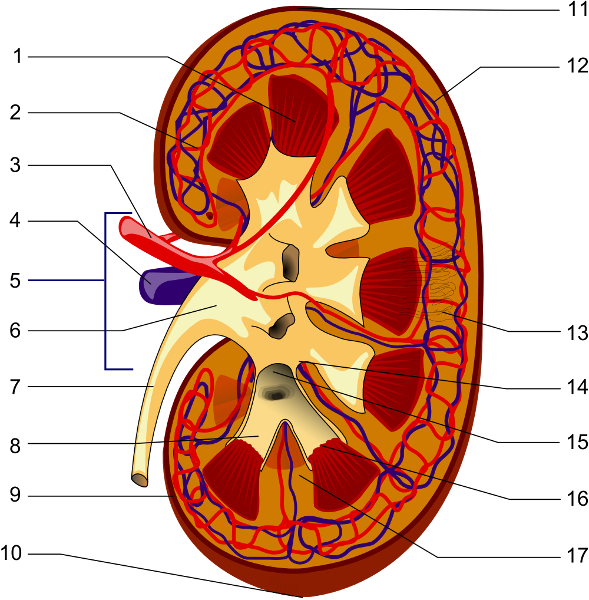

Afferent/efferent arteriole

Calyx (of the kidney)

Collecting duct

Descending/Ascending loop (of nephron)

Distal (convoluted) tubule

Glomerular capsule (=Bowman's capsule)

Glomerulus (=glomerular capillaries)

Juxtaglomerular apparatus

Medullary pyramids

Nephron

Peritubular capillaries

Proximal (convoluted) tubule

Renal artery/vein

Renal capsule

Renal columns

Renal corpuscle

Renal cortex

Renal medulla

Renal Pelvis